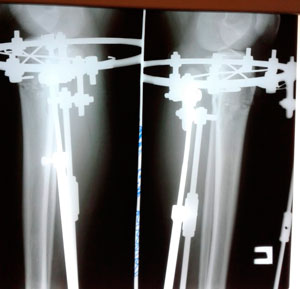

Рентген перед фиксацией

Вложения

IMG_4857-06-08-19-08-23.JPG

IMG_4856-06-08-19-08-23.JPG